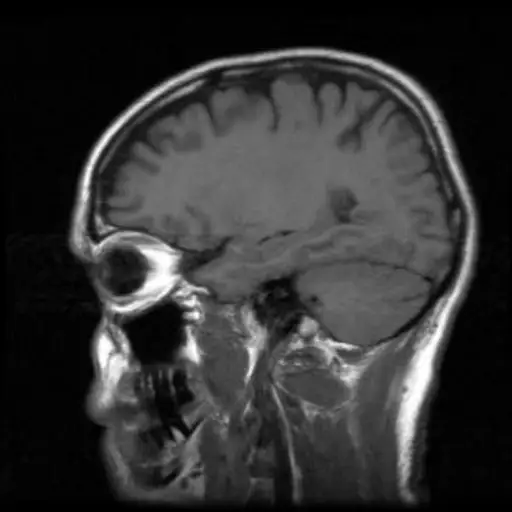

认知能力下降

消耗过多的钠量并且没有足够的锻炼可能有足够的成年人可能有一个增加认知衰落的风险根据最近的一项研究。许多研究发现,进气量会影响心脏健康,但该研究表明它也会影响脑健康。研究人员表示,该研究表明,使健康的生活方式选择成为人们的年龄。